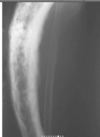

Cisto ósseo simples com fratura

Lesão litica unicameral.

Localização: úmero proximal e femur (< 20 anos) ou calcâneo, talus, ileo (> 20 anos).

Se fratura: Sinal do fragmento caído.